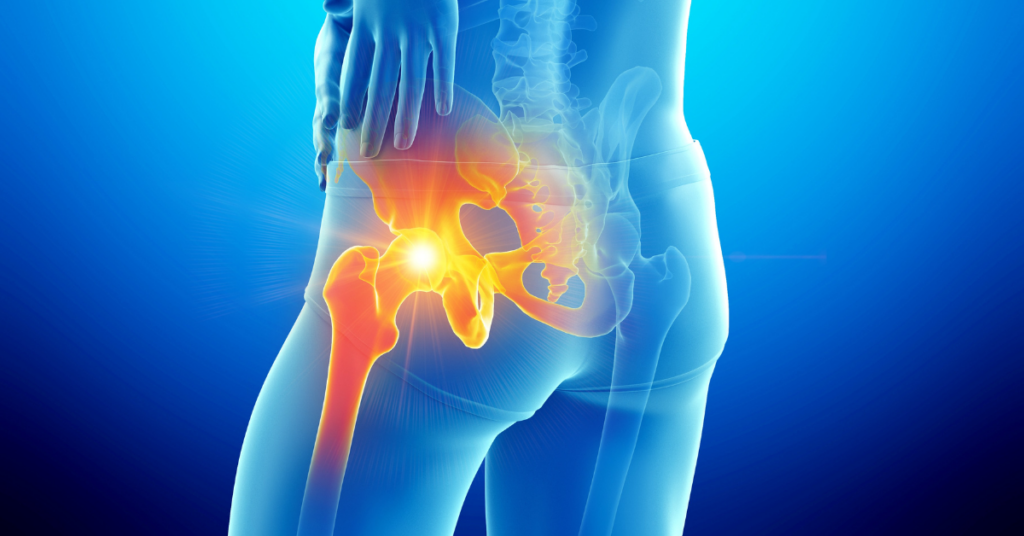

Sciatica isn’t a diagnosis on its own—it’s a symptom of something compressing, irritating, or inflaming the sciatic nerve, which runs from your lower back through your hips and buttocks and branches down each leg. The most common cause is a herniated or bulging lumbar disc pressing on a nerve root. Others include spinal stenosis, degenerative disc changes, bone spurs, or piriformis syndrome—a condition where the piriformis muscle deep in the buttocks compresses the nerve directly.

Why does the cause matter for hot tub therapy? Because different causes respond differently. Muscle-driven sciatica—particularly piriformis syndrome—often responds dramatically to heat and hydrotherapy because the treatment directly addresses the source. Disc-related sciatica frequently responds well too, though the hot tub manages symptoms rather than correcting the structural problem. Severe disc herniations or significant spinal stenosis may require medical intervention that hydrotherapy alone can’t provide.

Warm water penetrates deep into muscle tissue in a way that surface heating pads simply can’t replicate, allowing tight, guarding muscles to genuinely let go. For many sciatica sufferers, the experience of feeling those muscles release in warm water is immediate and unmistakable. For piriformis syndrome specifically, this deep heat targeting the piriformis muscle is often more effective than anything else patients report trying.

Submerged to shoulder level, your body carries roughly 10 percent of its normal weight. For a lumbar spine that’s been under gravitational compression all day—particularly one with a disc issue or narrowed spinal canal—this unloading creates real mechanical relief. Space opens between vertebrae. Pressure on nerve roots eases. Many people notice improvement in their symptoms within the first minute or two of immersion, before the heat has even had time to fully work.